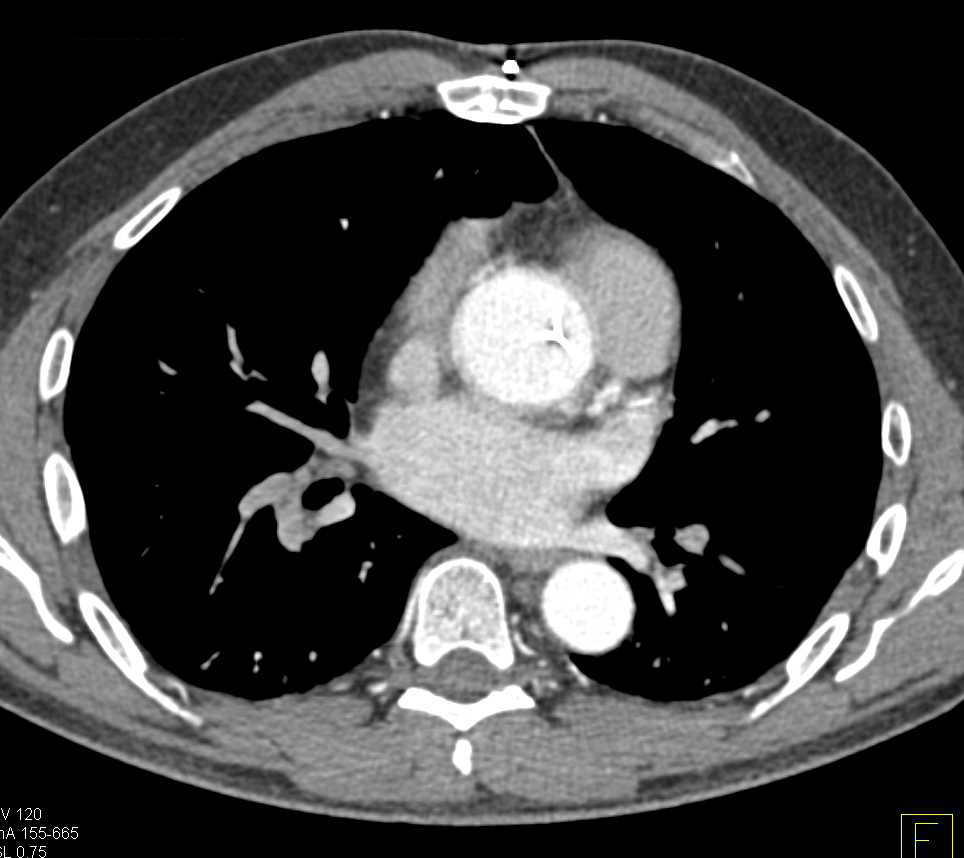

Extensive Pulmonary Embolism